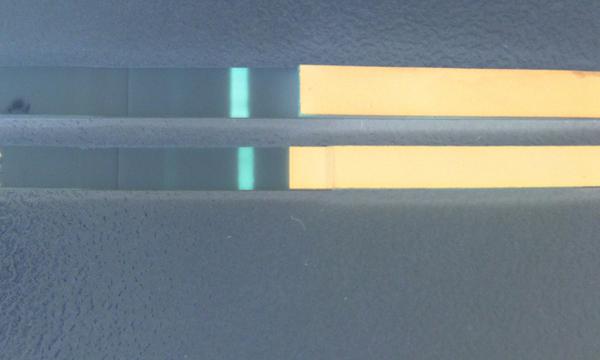

@dadenka111 Dušík je stále vidět a řekla bych, že je o malinko silnější než včera 🙂

@dadenka111 Já vidím rozhodně duch ajsněji než včera, to je dobré znamení 🙂 Velká gratulace, je to skvělý 🙂

@dadenka111 super, taky si myslím, že je silnější, než včera 🙂